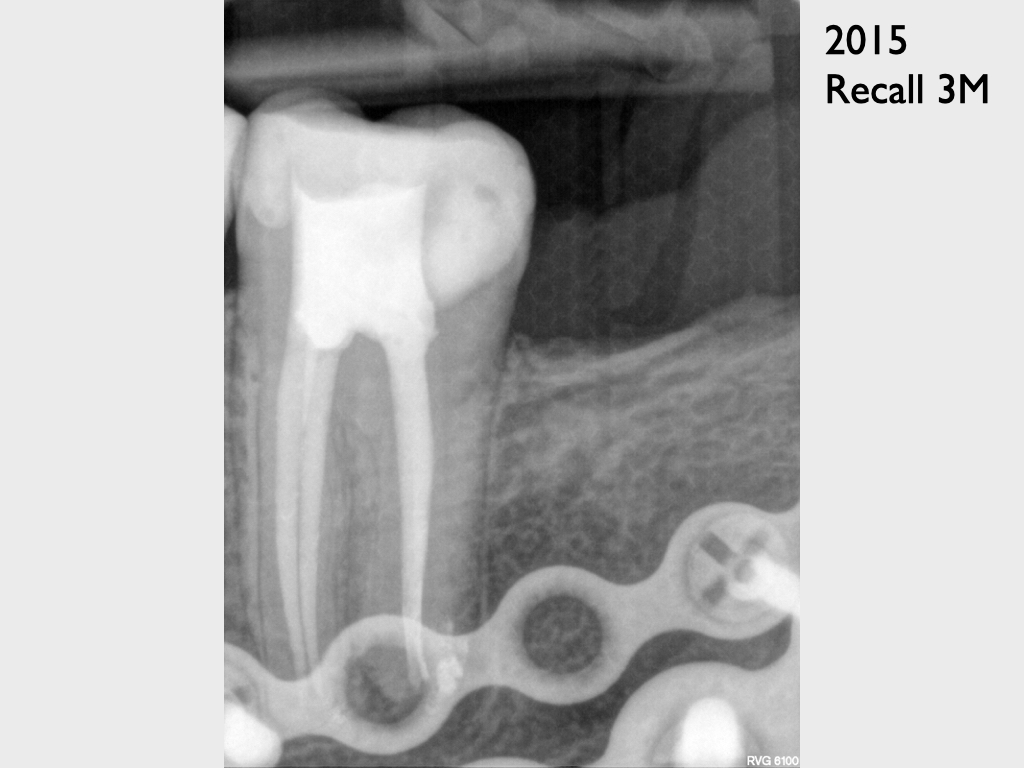

Zielschiessen